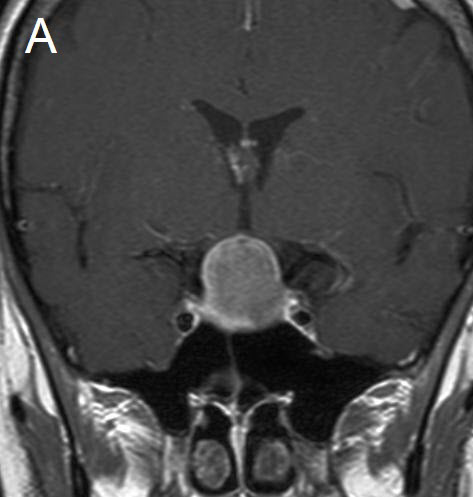

Figure 1 Illustrative case: Preoperative, intraoperative and postoperative imaging. A: Preoperative MRI, coronal view, contrast enhanced. B: Intraoperative MRI, coronal view, contrast enhanced, before skin incision. C: Intraoperative MRI, coronal view, contrast enhanced, during resection. D: Intraoperative MRI, coronal view, contrast enhanced, before closure. E: Postoperative MRI, coronal view, contrast enhanced.

A forty-two year old female was admitted for resection of a large pituitary adenoma. She complained about headache, amenorrhea and galactorrhea. Endocrinological diagnosis revealed a panhypopituitarism. The patient underwent surgery and the non-functioning pituitary adenoma could be totally removed. Postoperative follow-up showed normal pituitary function and the patient has now been in remission for 48 months. The figures show preoperative imaging, intraoperative imaging with various stages of the tumour resection, and postoperative follow-up MRI.